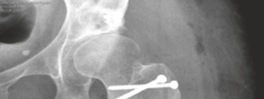

Trochanteric Re-fixation and Closure

- The trochanteric osteotomy fragment is meticulously re-positioned onto its anatomical bed.

- Fixation is typically achieved with two or three large-fragment cortical screws (e.g., 4.5 mm or 6.5 mm fully threaded screws) inserted through the trochanter into the lateral femoral cortex. Some surgeons prefer a tension band wiring technique or a combination. Secure fixation is paramount for early rehabilitation and prevention of nonunion.